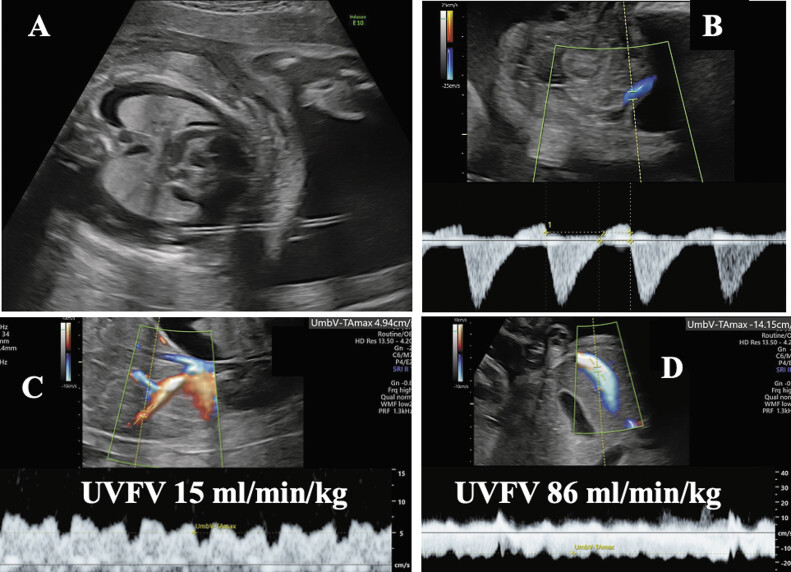

Objective: Although thoraco-amniotic shunting (TAS) for severe pleural effusion is an effective fetal treatment, there are some cases in which it deteriorates, showing circulatory collapse. To evaluate the usefulness of umbilical venous blood flow volume (UVFV) for predicting deterioration, we analyzed the fetal low UVFV situation.

Methods: In 22 cases of fetal severe pleural effusion, we measured UVFV/fetal estimated birth weight (mL/minute/kg) prospectively before and after TAS by ultrasonography. We defined low UVFV/kg as < 50 mL/minute/kg (2.5 percentile) and compared subgroups based on their UVFV value and analyzed the outcome after birth.

Results: Total survival rate was 59% at 6 months. Seven cases in the low group before delivery (UVFV/kg 19.5) showed poor prognoses, such as fetal/neonatal death and longer neonatal intensive care unit management (100% vs. the normal UVFV group 40%, p  = 0.017). The low group also showed umbilical artery absent end-diastolic velocity (71%); edema resolved in 50%, suggesting hypo inflow from the placenta and fetal hypocardiac output status, revealing fetal cardiac collapse.

Conclusion: UVFV analyses would be a new marker of fetal management of severe pleural effusion, suggesting low UVFV after TAS seems to be hypovolemic cardiac collapse and shows poor prognosis, and we had better consider immediate delivery to prevent death even after TAS.